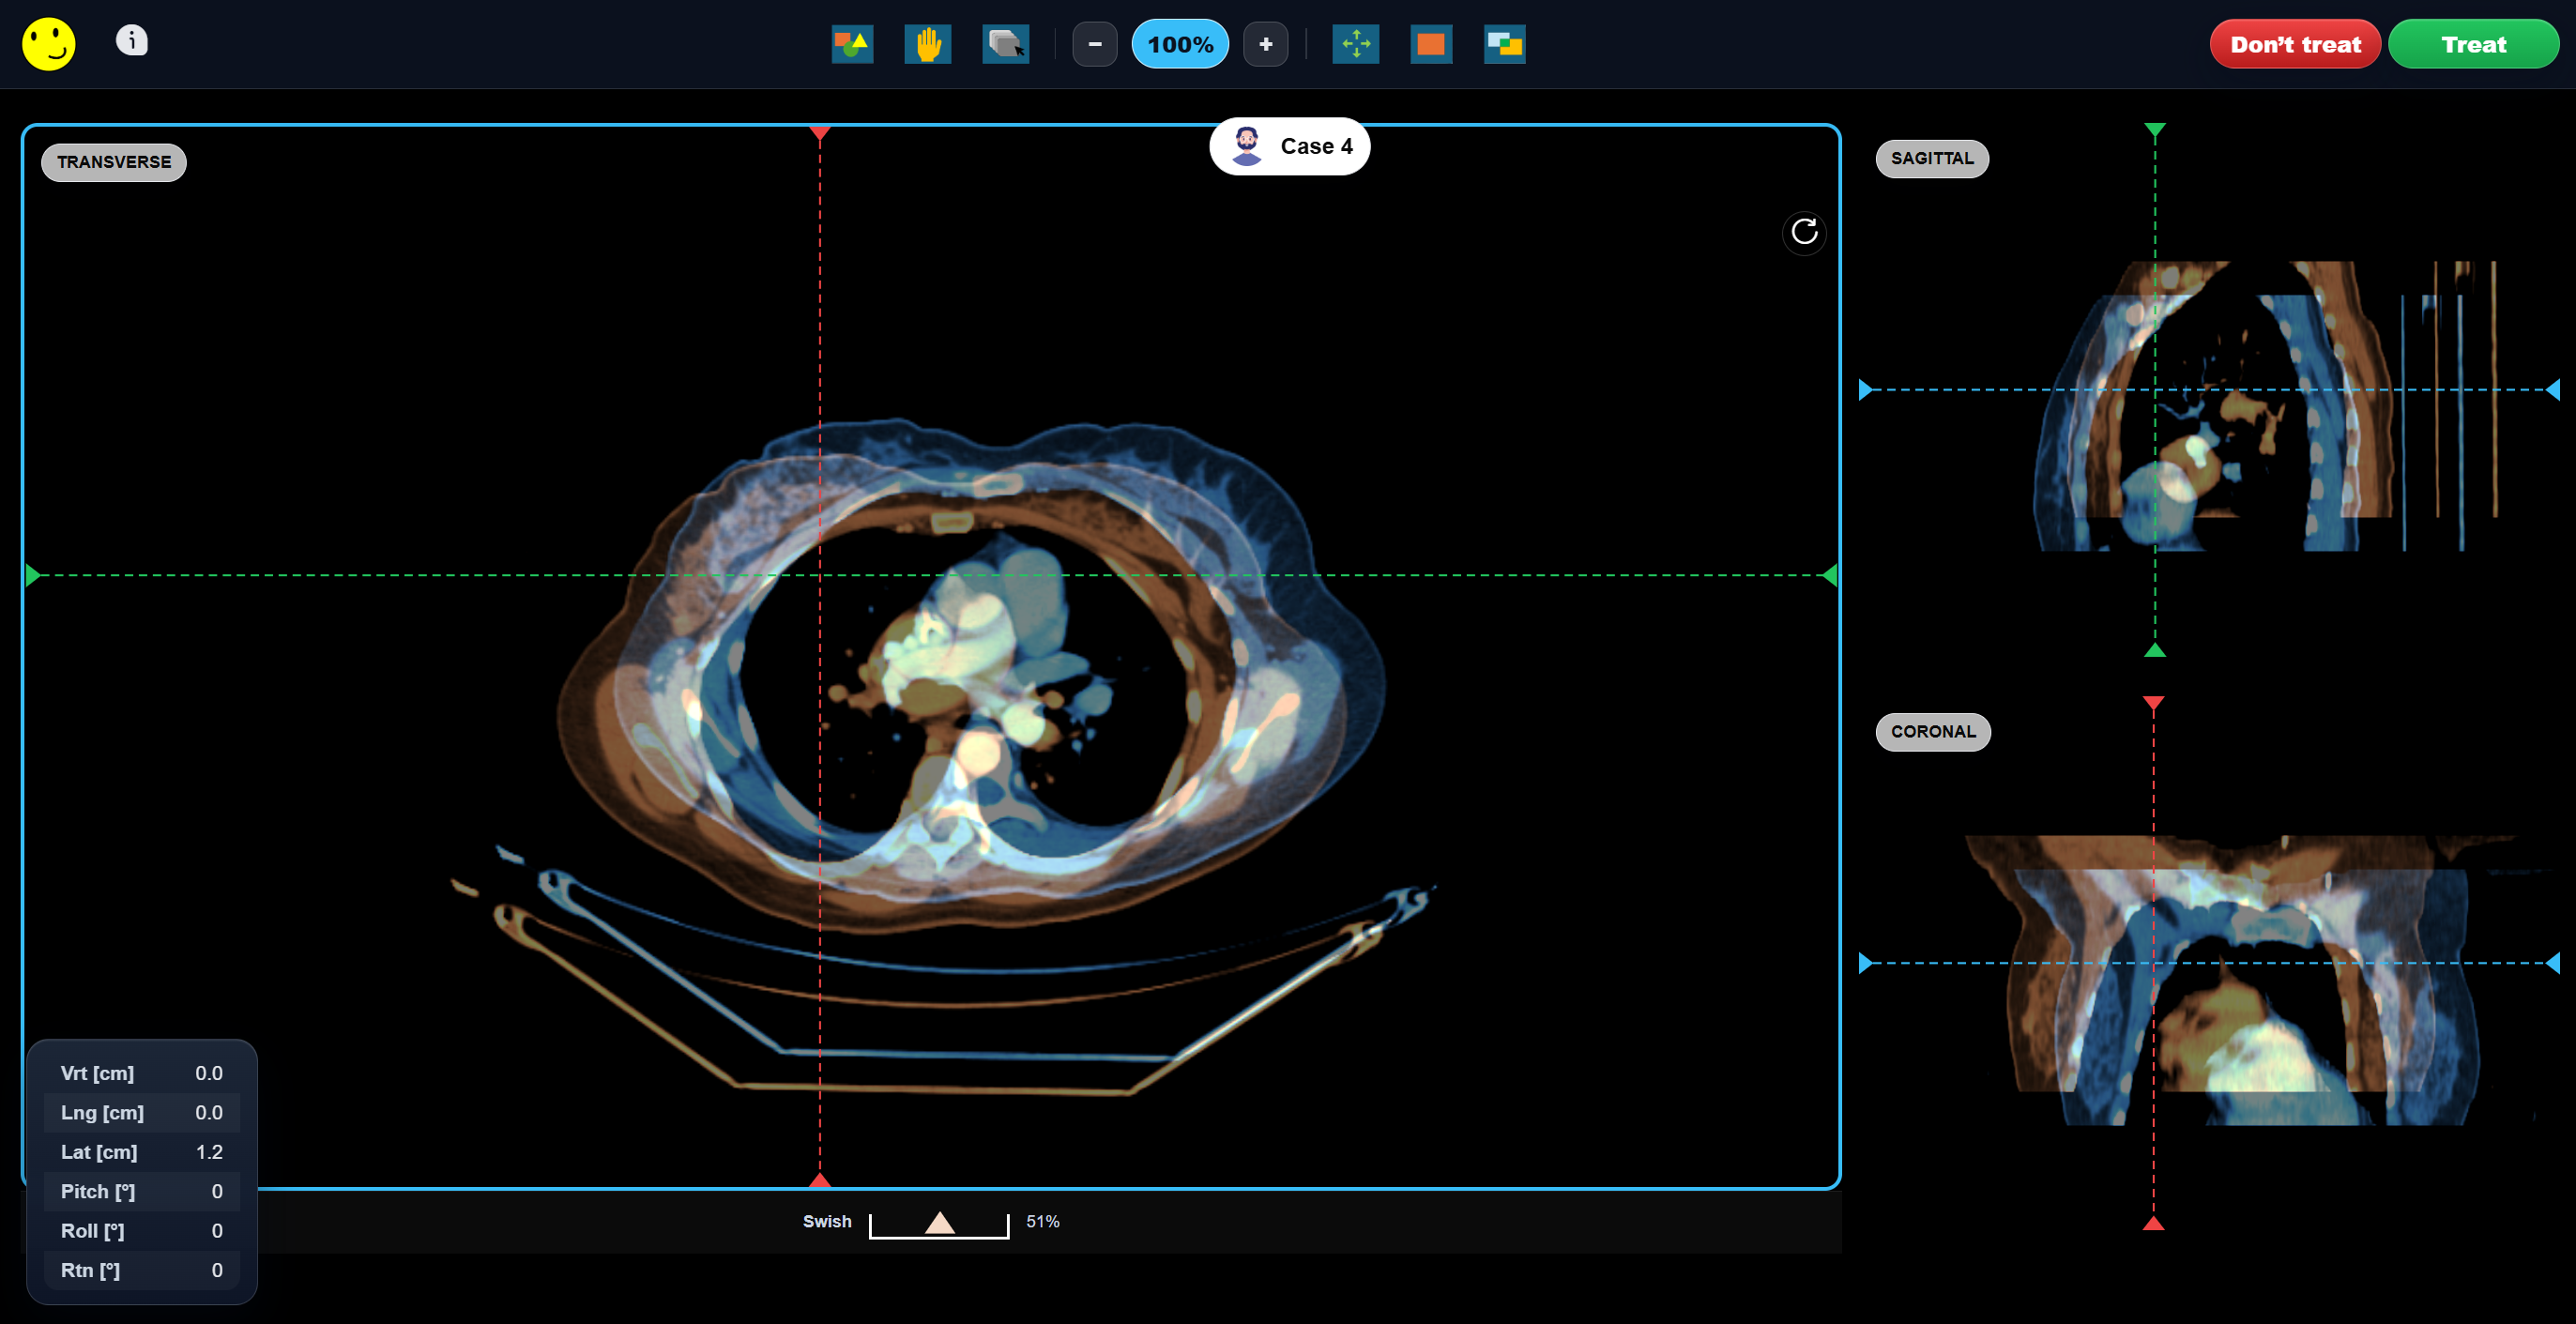

Image Matching

Practice with a growing library of real-world image matching cases and get feedback in real time. Line up anatomy, nudge the couch, and get instant feedback on whether you’re within training tolerances.

• Built around real radiotherapy image matching scenarios

We build image matching activities specifically for universities, helping support classroom teaching, guided sessions, homework, and OSCE/VIVA preparation.